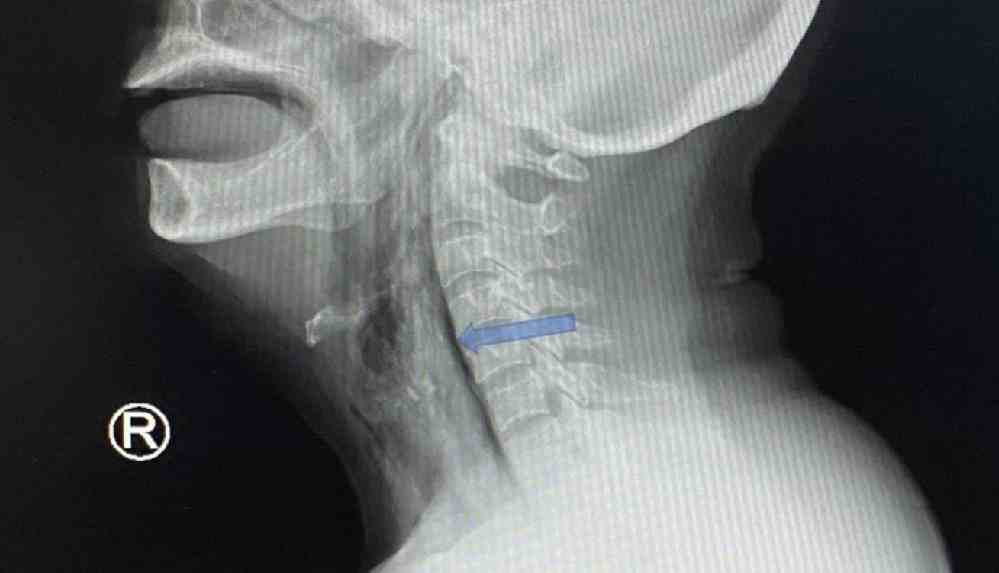

Selayang Hastanesi’ndeki doktorlar, acil servise gelen hastada kılçığı ilk başta bulamadı. Zira boğaza bakıldığında kılçık gözükmezken, çekilen röntgen de başarısız oldu.

Independent Türkçe’nin haberine göre, daha sonra yapılan bilgisayarlı tomografi taraması, 5,1 santimetrelik kılçığın sternokleidomastoid adlı boyun kasına gömüldüğünü ortaya koydu.